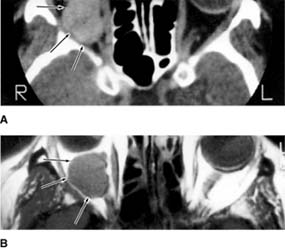

Cavernous hemangiomas are benign, grow slowly, and usually become symptomatic in middle life. Most occur in women. They most often lie within the muscle cone, producing axial proptosis, hyperopia, and, in many cases, choroidal folds. Unlike capillary hemangiomas, they do not tend to regress spontaneously. Surgical excision is usually successful and is indicated if the patient is symptomatic.

Figure 13-7: Cavernous hemangioma (arrows) of the right orbit as demonstrated by both CT scan (A) and MRI (B). The left side demonstrates the appearance of a normal orbit and globe. (Courtesy of D Char.)